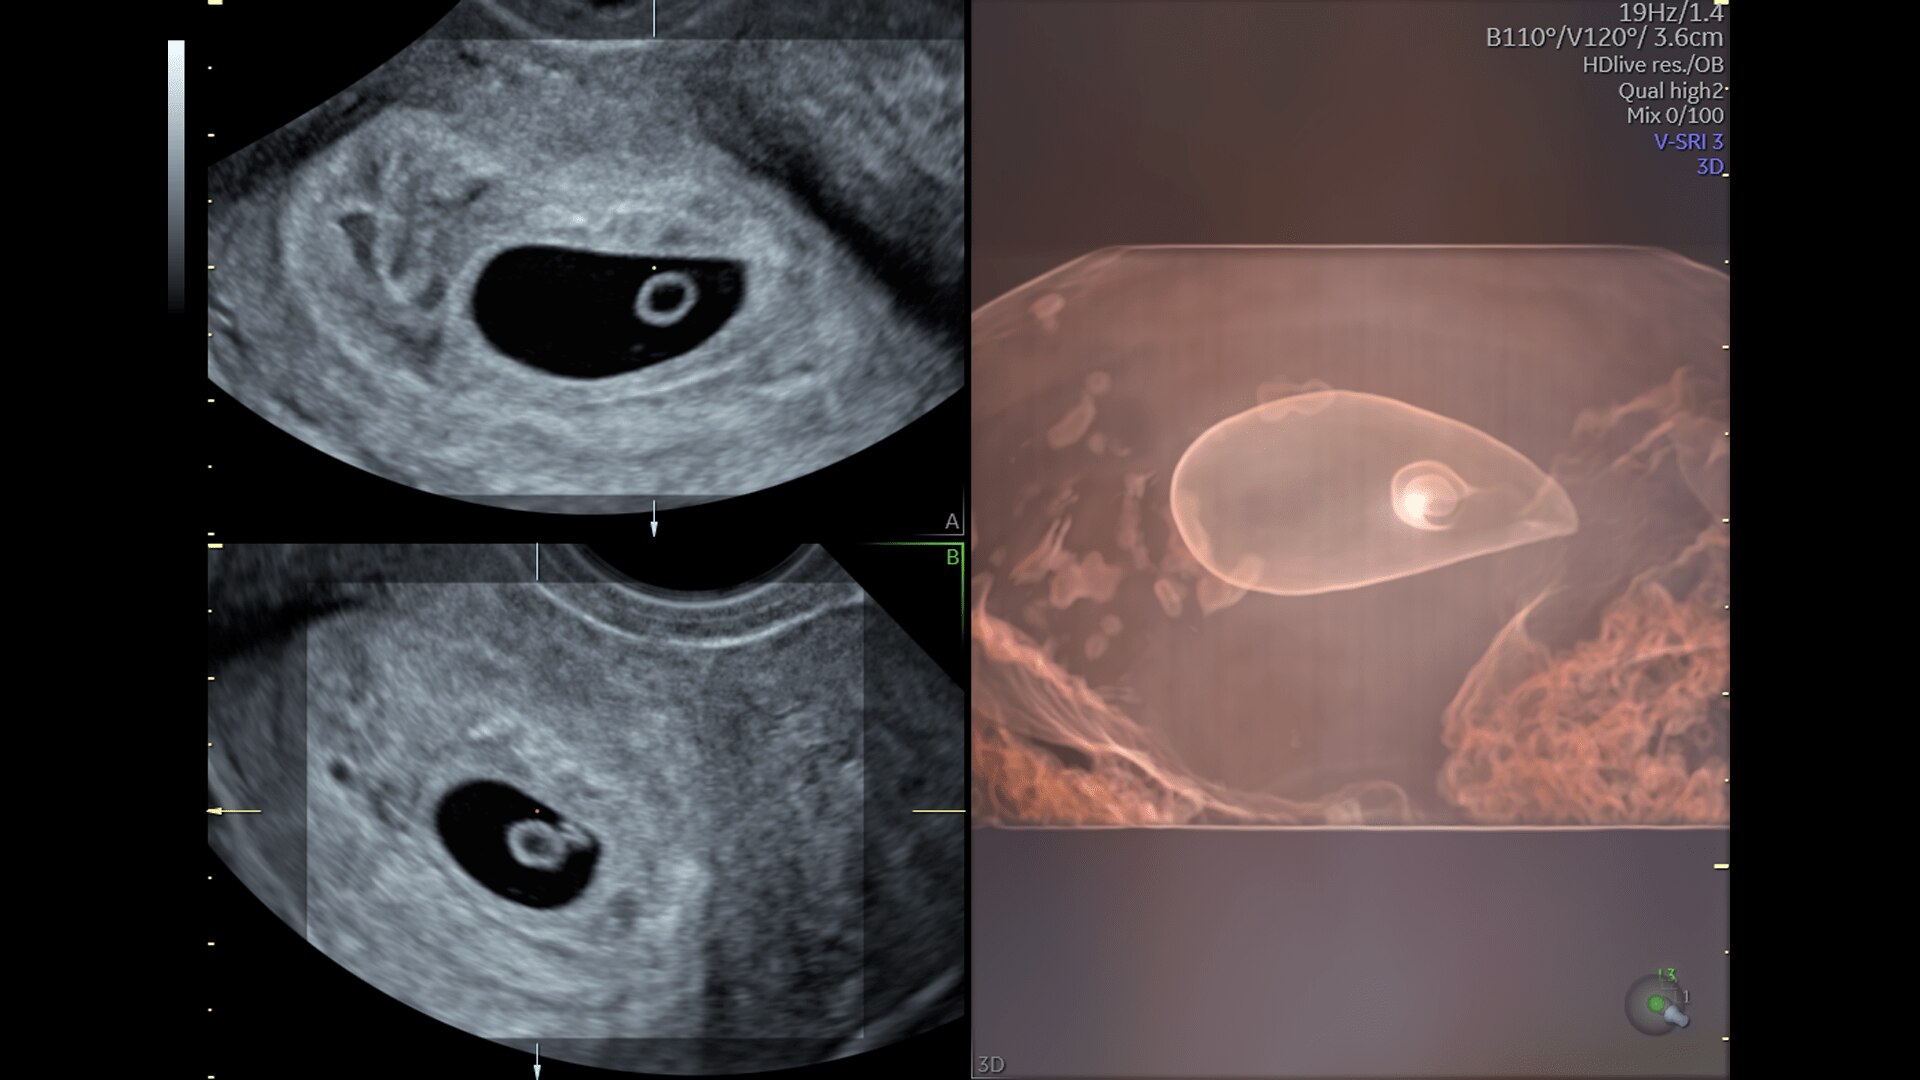

First Trimester Exams

Perform detailed exams with high-resolution for early insights to fetal health

Complex cases come with enough uncertainty. That's why the Voluson Expert 22 is specifically designed for in-depth assessment of complicated anatomy — with pioneering first trimester, fetal cardiac, gynecological, and other pivotal technologies that focus on early detection and intervention.